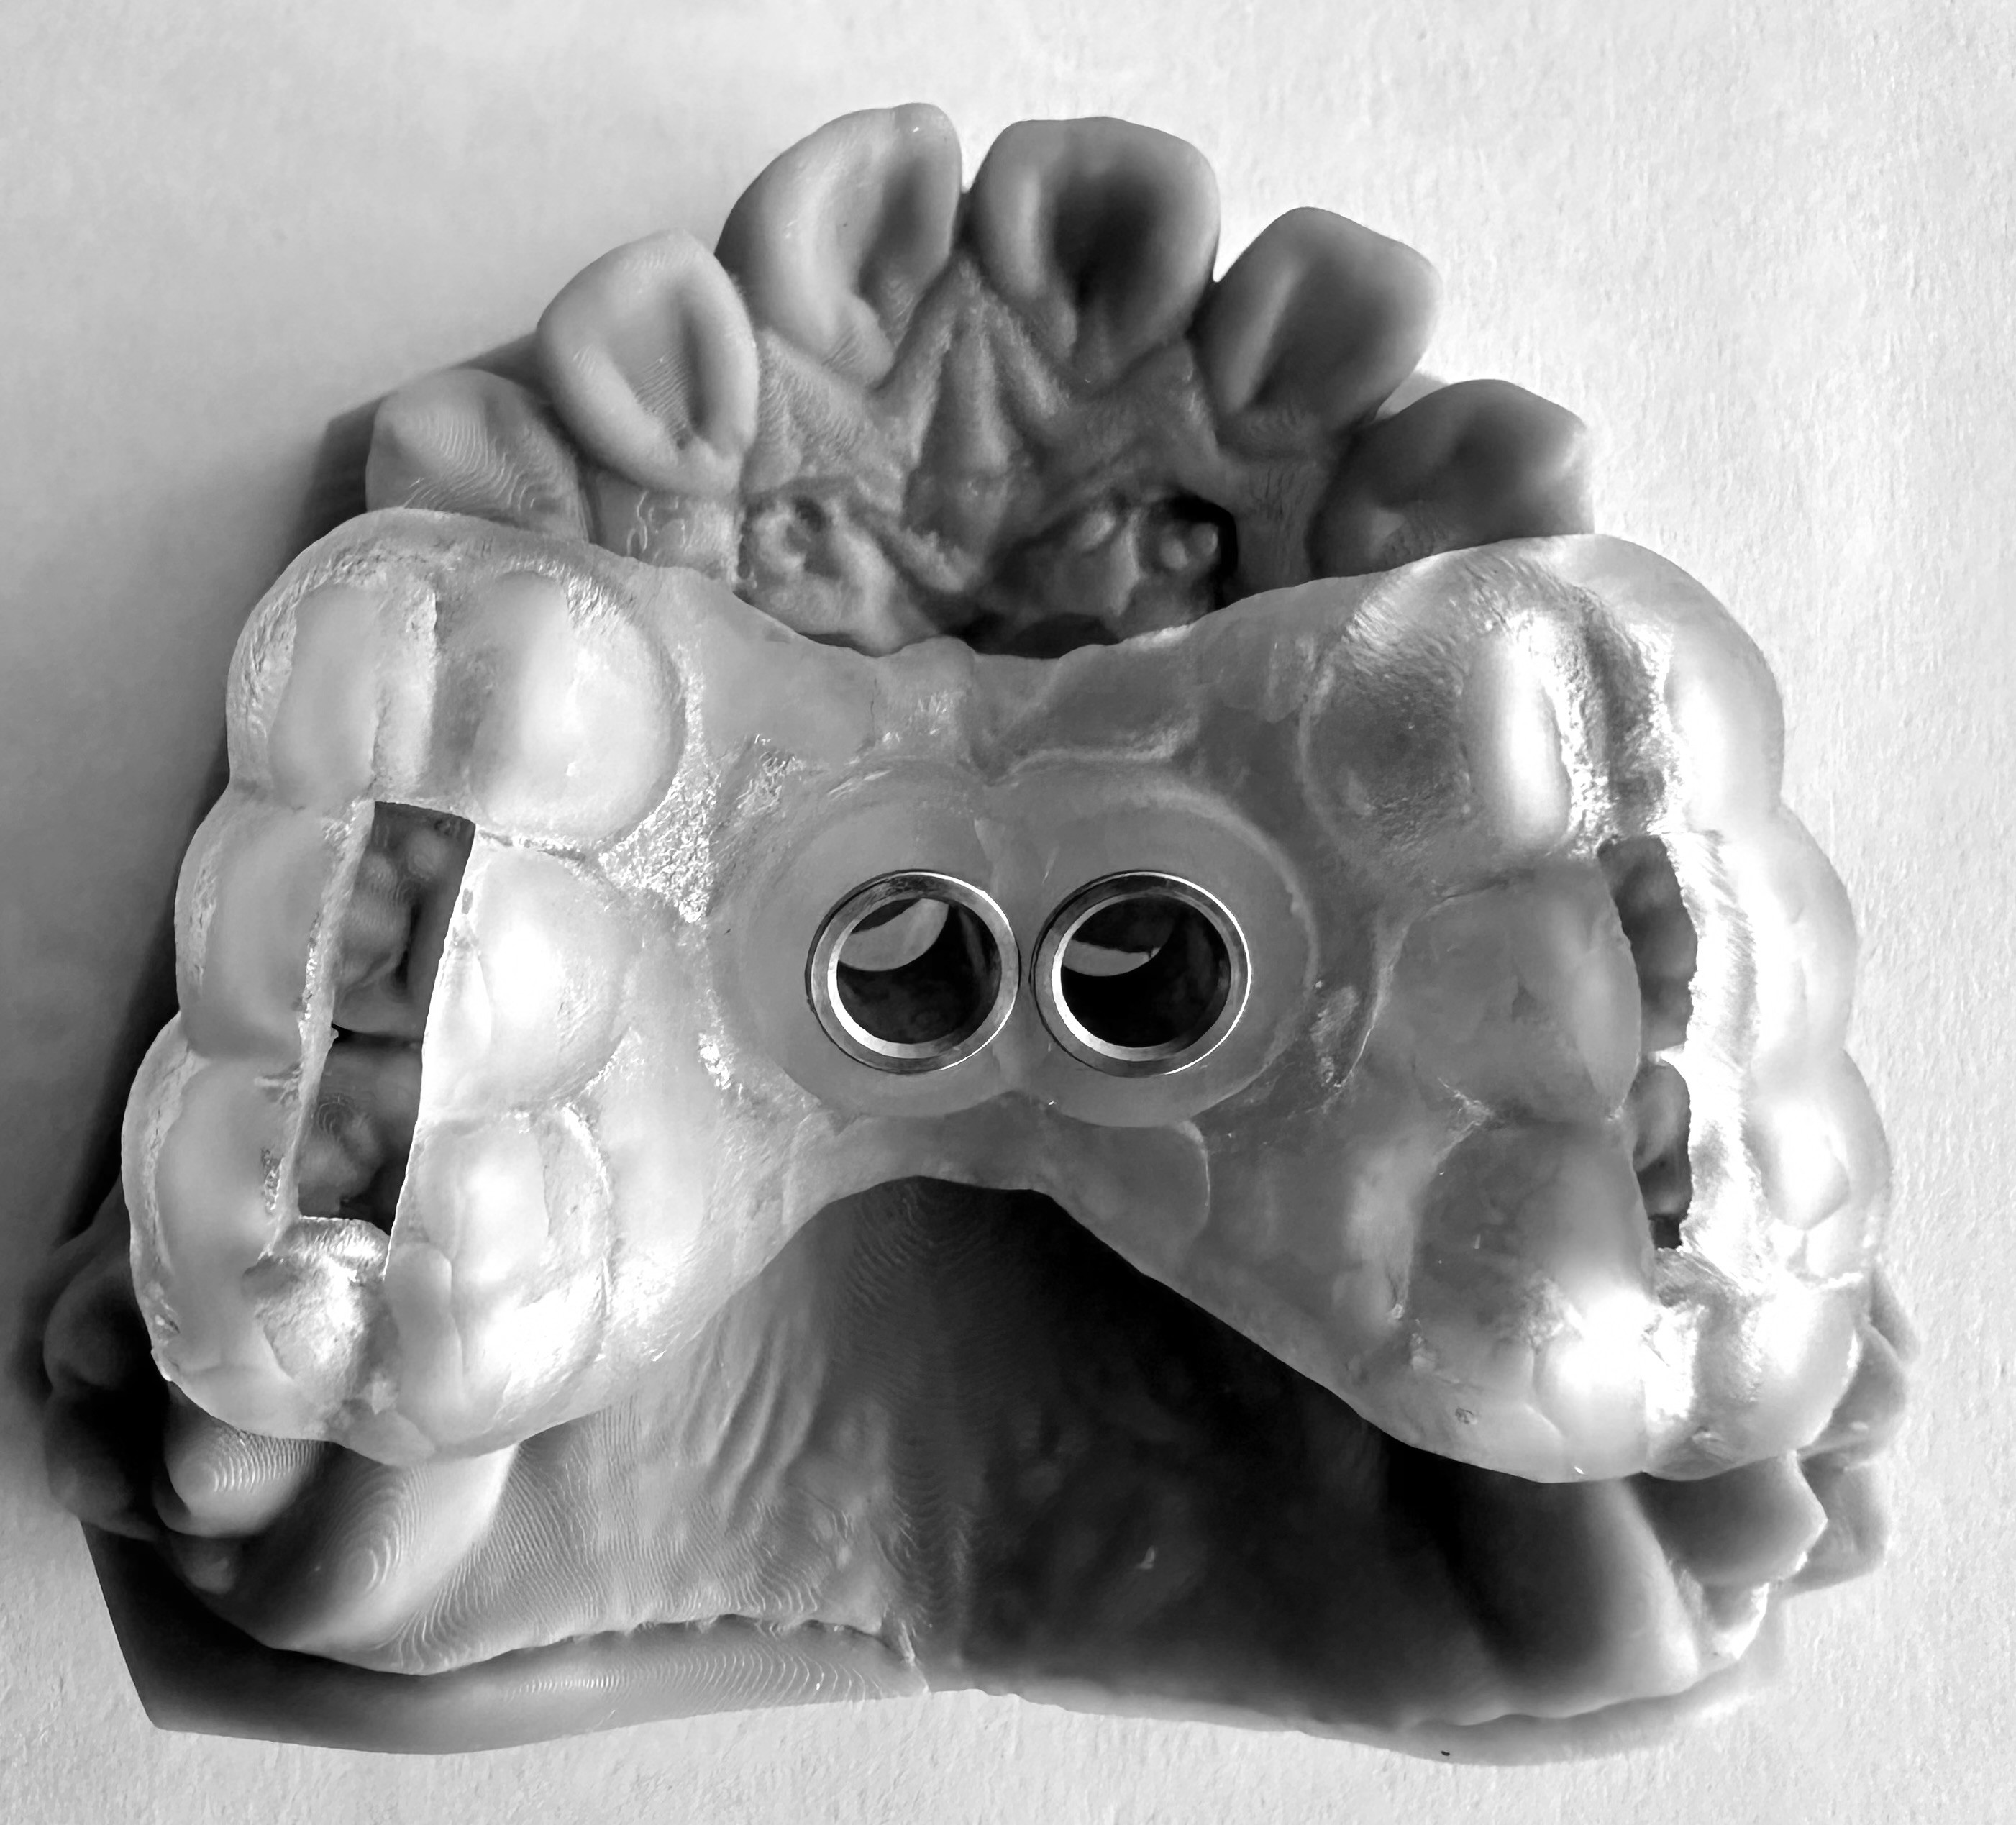

Anclaje esquelético MARPE guiado.

3. XCROSS/EXPANSIÓN: La tercera llave es la integración. Cuando biomecánica, cirugía y tecnología se alinean, los límites desaparecen, se amplian las fronteras. Ni la edad ni la complejidad son barreras cuando hay protocolo guiado. Lo que antes era imposible, hoy se resuelve con confianza.